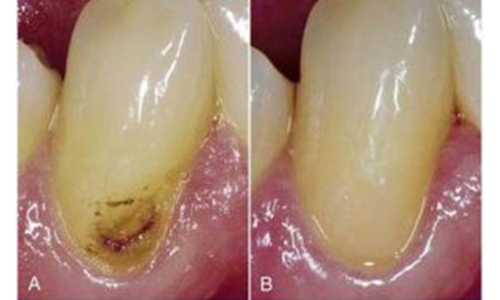

GIC has fluoride releasing capacity which makes it anticariogenic. Fluoride release helps in prevention of caries. It bonds chemically with the tooth.

GIC is usually avoided in back teeth due to their less strength. They are mostly used in pediatric patients.

Steps in GIC restoration

It is a single sitting procedure. Caries are excavated and then tooth is properly isolated. GIC is placed and petroleum jelly is applied on the surface to avoid its dehydration. Patient should avoid water or food for next 30-60 min.